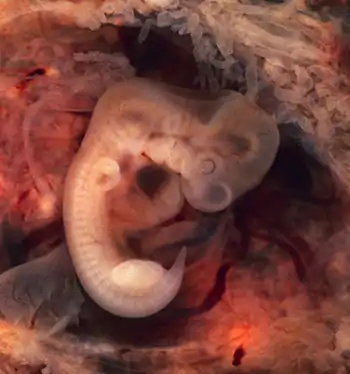

Tubal pregnancy

The vast majority of ectopic pregnancies implant in the fallopian tube. Pregnancies can grow in the fimbrial end (5% of all ectopic pregnancies), the ampullary section (80%), the isthmus (12%), and the cornual and interstitial part of the tube (2%).[24] Mortality of a tubal pregnancy at the isthmus or within the uterus (interstitial pregnancy) is higher as there is increased vascularity that may result more likely in sudden major internal bleeding. A review published in 2010 supports the hypothesis that tubal ectopic pregnancy is caused by a combination of retention of the embryo within the fallopian tube due to impaired embryo-tubal transport and alterations in the tubal environment allowing early implantation to occur.[35]

While a fetus of ectopic pregnancy is typically not viable, very rarely, a live baby has been delivered from an abdominal pregnancy. In such a situation the placenta sits on the intra-abdominal organs or the peritoneum and has found sufficient blood supply. This is generally bowel or mesentery, but other sites, such as the renal (kidney), liver or hepatic (liver) artery or even aorta have been described. Support to near viability has occasionally been described, but even in Third World countries, the diagnosis is most commonly made at 16 to 20 weeks' gestation. Such a fetus would have to be delivered by laparotomy. Maternal morbidity and mortality from extrauterine pregnancy are high as attempts to remove the placenta from the organs to which it is attached usually lead to uncontrollable bleeding from the attachment site. If the organ to which the placenta is attached is removable, such as a section of bowel, then the placenta should be removed together with that organ. This is such a rare occurrence that true data is unavailable and reliance must be made on anecdotal reports.[37][38][39] However, the vast majority of abdominal pregnancies require intervention well before fetal viability because of the risk of bleeding.